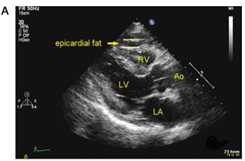

Η πρώτης γραμμής μέθοδος για τη μέτρηση του επικαρδίου λίπους είναι η δυσδιάστατη διαθωρακική ηχοκαρδιογραφία, που είναι μια ασφαλής, εύκολα αναπαραγώγιμη και μη επεμβατική μέθοδος που μπορεί να γίνεται τακτικά σε ασθενείς με υποψία καρδιαγγειακής νόσου ή κίνδυνο μεταβολικού συνδρόμου (εικόνα 3).

Εικόνα 3: Πάχος επικαρδιακού λίπους στο υπερηχοκαρδιογράφημα. Ορίζεται ως ο σχετικά ελεύθερος ήχου χώρος μεταξύ του εξωτερικού τοιχώματος του μυοκαρδίου και το σπλαχνικό στρώμα του περικαρδίου.

Ao: αορτή, LA: αριστερός κόλπος, LV: αριστερή κοιλία, RV: δεξιά κοιλία.

Παρά τα πλεονεκτήματα, το υπερηχοκαρδιογράφημα δεν είναι η βέλτιστη τεχνική για τον ποσοτικό προσδιορισμό του επικαρδιακού λίπου, αφού δεν μετρά τον συνολικό όγκο του.